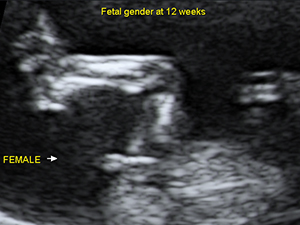

Gender - Female

Female genital organ (arrow) at 20 weeks